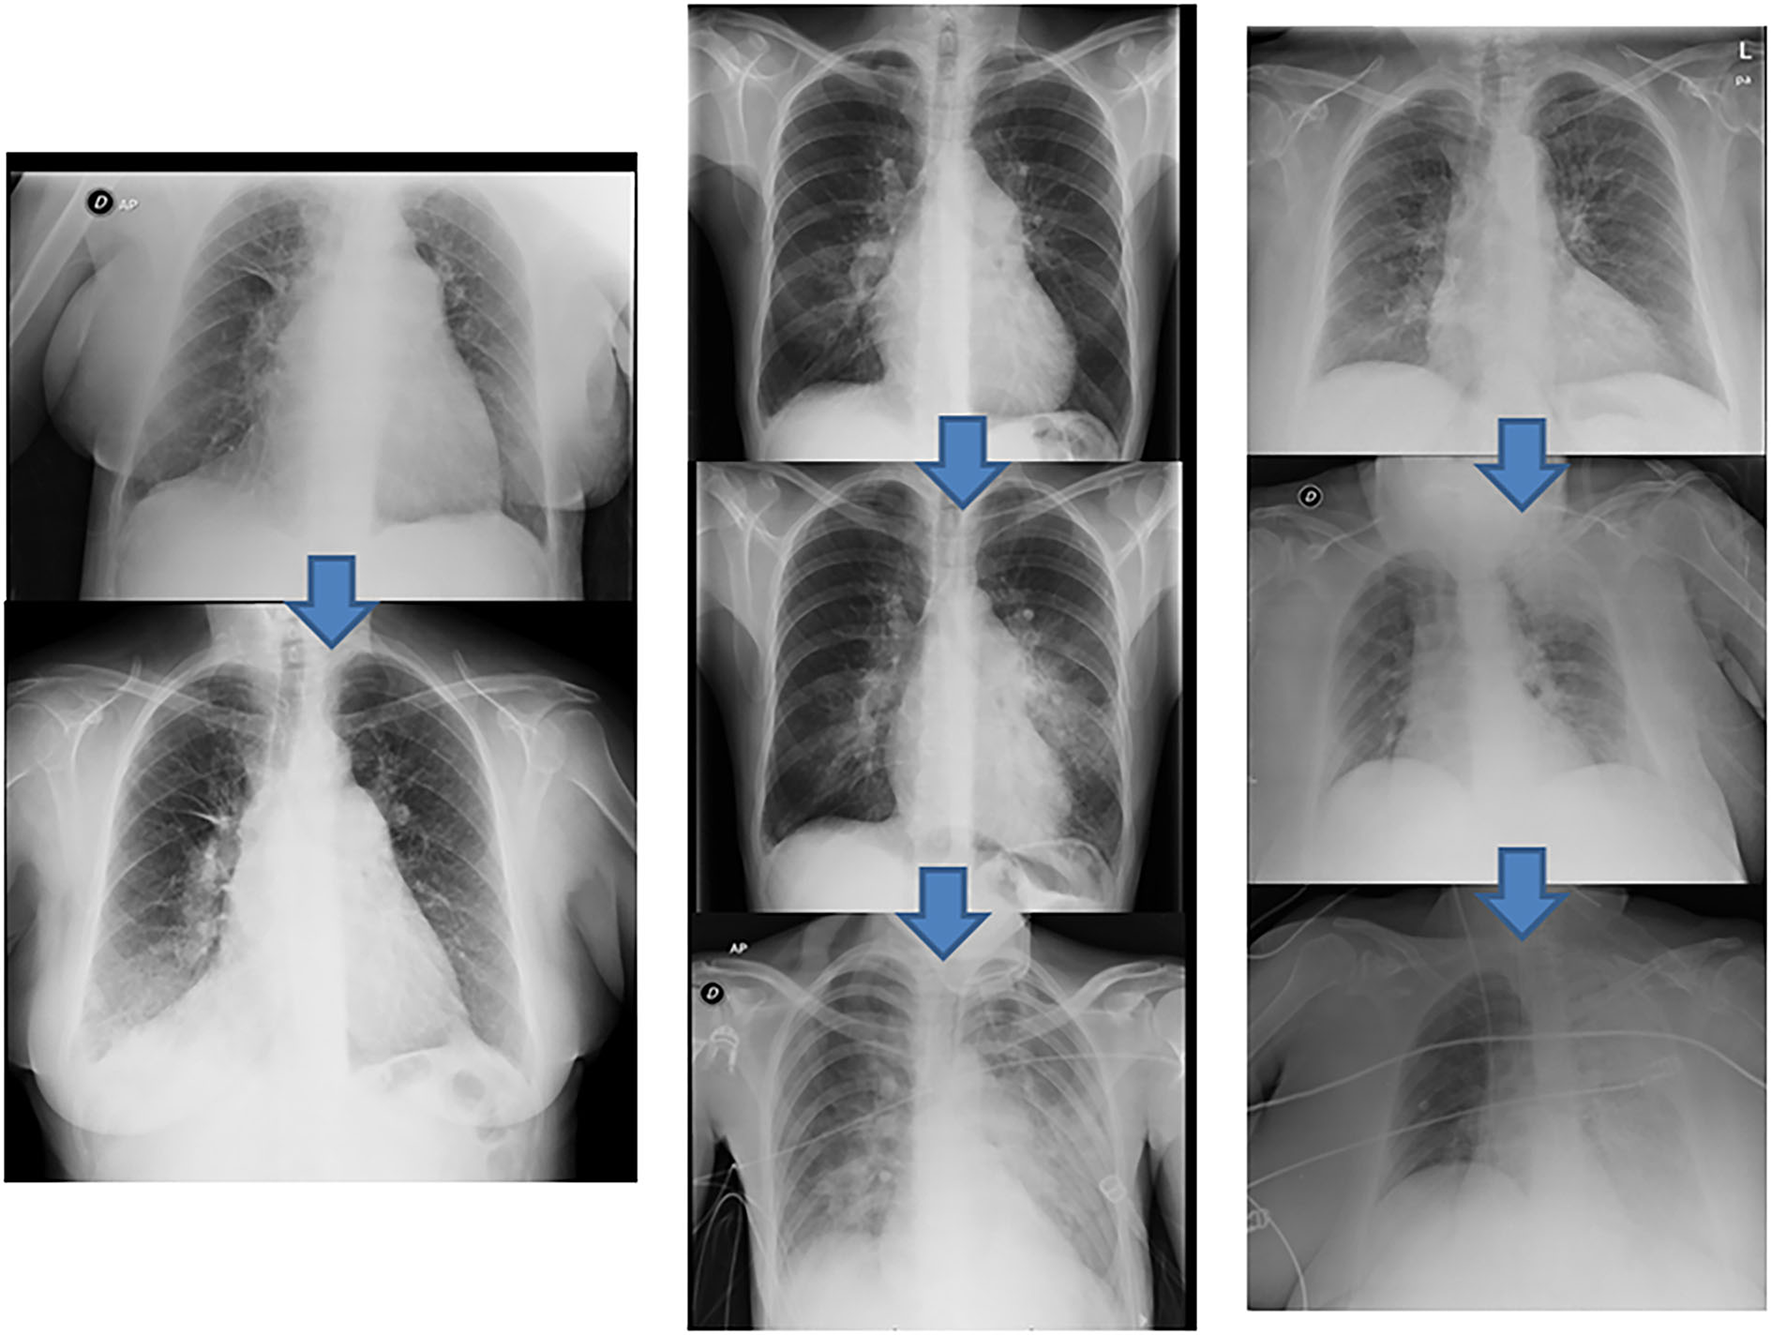

Figure 6

Radiologic pulmonary injury expression. Examples of different degrees of reperfusion edema according to their radiological expression. (Left) grade 3 reperfusion edema, infiltration in the right lower lobe (above pre-BPA baseline chest radiograph). (Center) grade 4 reperfusion edema, infiltration in the lingula extending to the contralateral lung (above pre-BPA baseline chest radiograph). (Right) grade 5 reperfusion edema, initial infiltration in the left upper lobe that eventually spreads to the entire left lung (above pre-BPA baseline chest radiograph). BPA, balloon pulmonary angioplasty.

Across all 116 procedures performed on 33 patients, the most common complication was mild hemoptysis, which occurred in 21.2% of the patients throughout the program and in 12.9% of the procedures. This complication was resolved in all patients by stopping the procedure, along with anticoagulation reversal and prolonged balloon inflation when necessary (Supplementary Videos 3–5). None of the patients with this complication required ventilatory or hemodynamic support. One patient underwent covered stent implantation due to a bronchopulmonary artery fistula (Figure 5). The pulmonary injury appeared in 3.4% of the procedures, of which 50% were grade 2 (Figure 6). No patient aged ≥70 years had a grade 5 pulmonary injury. One patient who was admitted to undergo several BPA procedures died 96 h after her first BPA session due to a hemorrhagic stroke while receiving LMWH at an anticoagulant dose (periprocedural mortality, 3%) (Table 5).